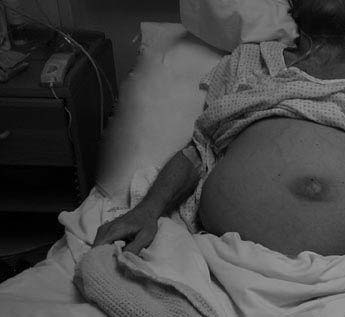

Hình 3: Bịnh nhân bị nước ứ trong phúc mạc (ascites) và vàng da (jaundice) do xơ gan (cirrhosis).(Source: documenting reality.com)

Người xơ gan nặng có thể được thoải mái hơn nhờ các thuốc lợi tiểu (diuretic), thuốc hạ áp huyết, theo dõi tình trạng cơ năng gan và khả năng xuất hiện ung thư gan, chữa những triệu chứng của bịnh não bộ do bịnh gan gây ra. Biện pháp cuối cùng nếu gan không làm việc được là ghép gan mới (từ xác chết hoặc người cho sống ( liver transplant)).